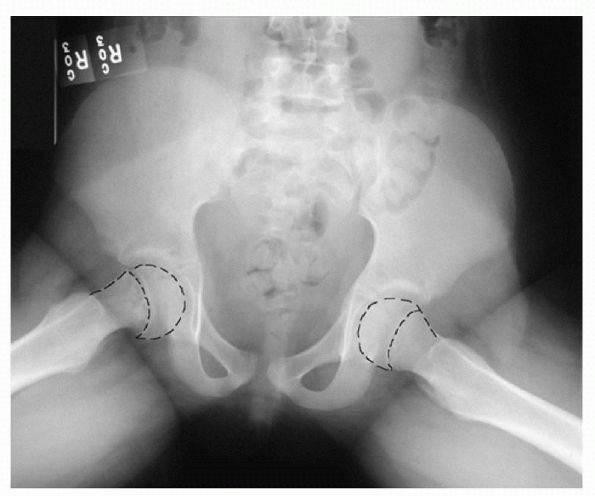

![]() |

Figure 11-1 Anteroposterior pelvis radiograph showing widening of the right proximal femoral physis.

Widening of the physis (Fig. 11-1)

Subtle displacement of the metaphyseal/epiphyseal relationship (Fig. 11-2)

Asymmetry of Klein’s line, most pronounced on AP projection (Fig. 11-3)

Figure 11-2 Frog-leg radiograph showing mild epiphysical displacement on the right side.

Figure 11-3 Anteroposterior radiograph of a mild slip of the right femoral epiphysis and correspondingasymmetry of Klein’s line.

Figure 11-4

Frog-leg radiograph of bilateral chronic slips, after pinning, demonstrating varus deformity and metaphyseal remodeling and sclerosis. |